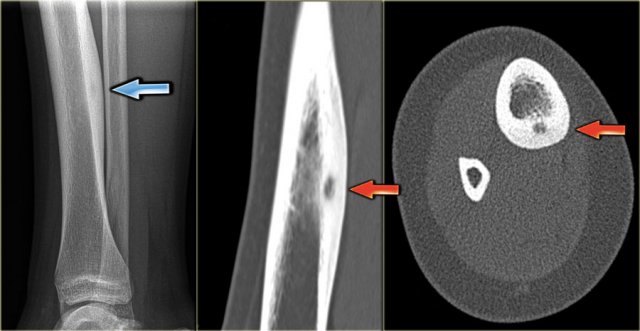

Here CT-images of a patient with renal failure and multiple well-defined osteolytic lesions.

The differential diagnosis included metastases, multiple myeloma and Brown tumors in hyperparathyroidism.

Biopsy revealed Brown tumor.